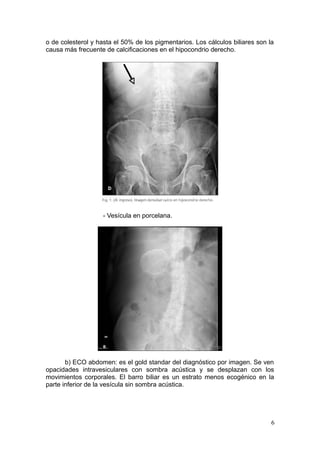

- Cálculos radiopacos: que son hasta el 15% de los mixtos

5

o de colesterol y hasta el 50% de los pigmentarios. Los cálculos biliares son la

causa más frecuente de calcificaciones en el hipocondrio derecho.

- Vesícula en porcelana.

b) ECO abdomen: es el gold standar del diagnóstico por imagen. Se ven

opacidades intravesiculares con sombra acústica y se desplazan con los

movimientos corporales. El barro biliar es un estrato menos ecogénico en la

parte inferior de la vesícula sin sombra acústica.